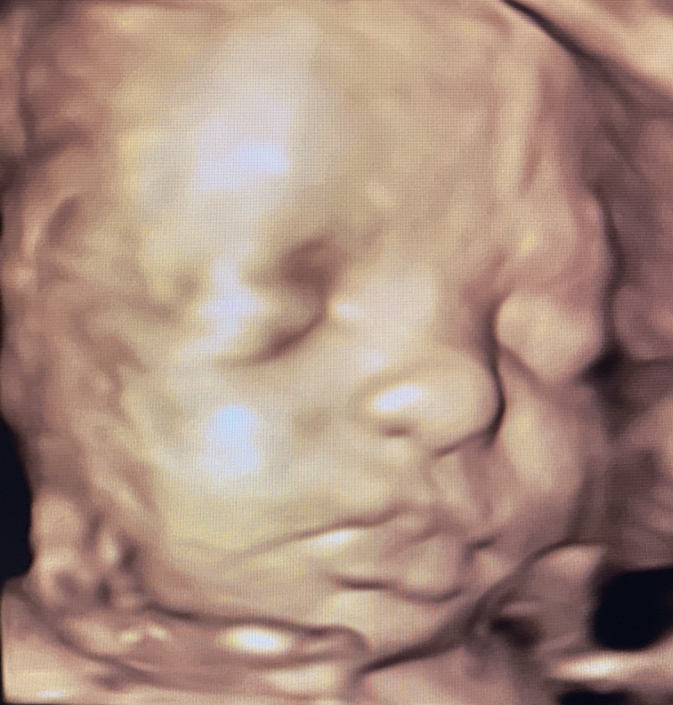

Prenatal Peek®

Prenatal Peek is the leader in 3D 4D Ultrasound. We employ only Certified / Registered Sonographers maintaining unsurpassed standards in 3D ultrasound. You deserve the best! Call us today.